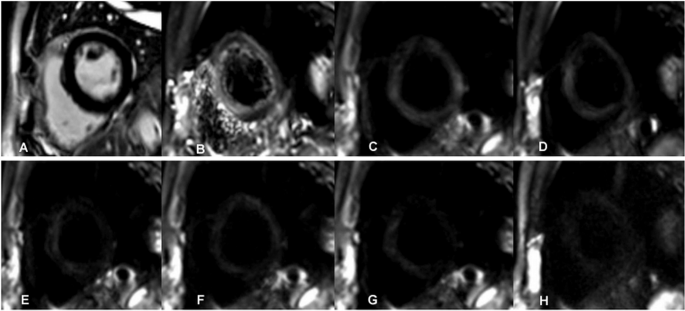

A male patient aged 56 years with old myocardial infarction. (A) Magnetic resonance imaging (MRI) with delayed enhancement was performed with LGE (late gadolinium enhancement)-positive area of infarction indicated by the arrows. B-H. IVIM-DWI images of the same patient. The IVIM-DWI images were shown with b values of 0 (B), 20 (C), 60 (D), 80 (E), 120 (F), 200 (G), and 600 (G) s/mm2. Both the signal intensity of the infarcted myocardium and cardiac blood pool demonstrated high signal intensity. With the increase in the b value, the signal intensity of the blood pool decreased, with an optimal contrast at bā=ā120ās/mm2. IVIM, intravoxel incoherent motion; DWI, diffusion-weighted image.